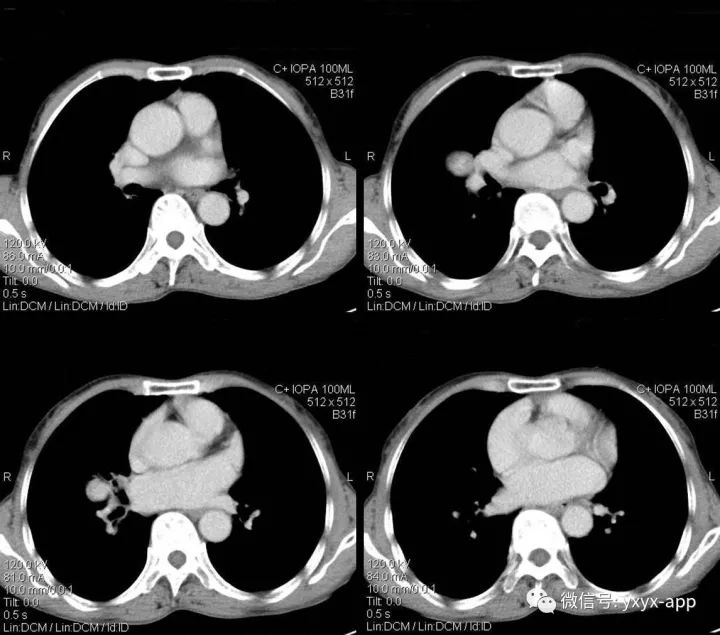

肚肚丫头:右肺门结节影,边界清,密度尚均匀,增强扫描动脉期,病变呈轻度强化,静脉期强化明显(与血管相当),病灶部分与支气管相贴。纵隔未见肿大的淋巴结。考虑与血管相关的良性病变可能。1.硬化性血管瘤;2. 巨淋巴结增生不除外

1.病灶为圆形或类圆形,边缘光滑,无毛刺,少数可有分叶,约70%病灶直径小于3cm。肿瘤无包膜,钙化率可达40%以上,可有囊变。

2.CT平扫病灶密度较均匀,与肌肉密度相近,多数PSH增强扫描动脉期有所强化,静脉期及延迟期持续均匀强化;少数为不均匀强化。较小病灶以血管瘤型和乳头型为主,强化较明显且均匀;随着病灶增大,实体型和硬化型成分逐渐增多,强化程度随之减低且不均匀。

本例特点为①病灶为圆形,小于3cm,边缘光滑,无钙化及囊变;②肿瘤增强扫描为动脉期有所强化,静脉期持续均匀强化,与同层肺动脉相近;③相对特殊征象:仅见动脉期贴边血管征,未见空气新月征及尾征。本例主要要与肺无脂肪和钙化的错构瘤鉴别,以及炎性肌纤维母细胞瘤鉴别,后两者均不具有持续均匀强化的特点,可做鉴别。而巨淋巴结增生症动脉期明显强化,静脉期回落,与本例强化时相不符。